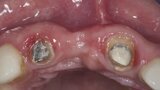

Biomodulacja laserem Nd:YAG z użyciem głowicy Genova®